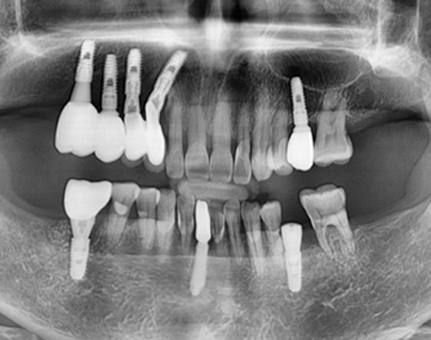

문치과 임플란트 사례

모든 전후 사진은 단순한 비교가 아닌,

환자분의 고민과 변화의 기록입니다.

문치과는 각자의 사연에 맞는 해답을 찾습니다.